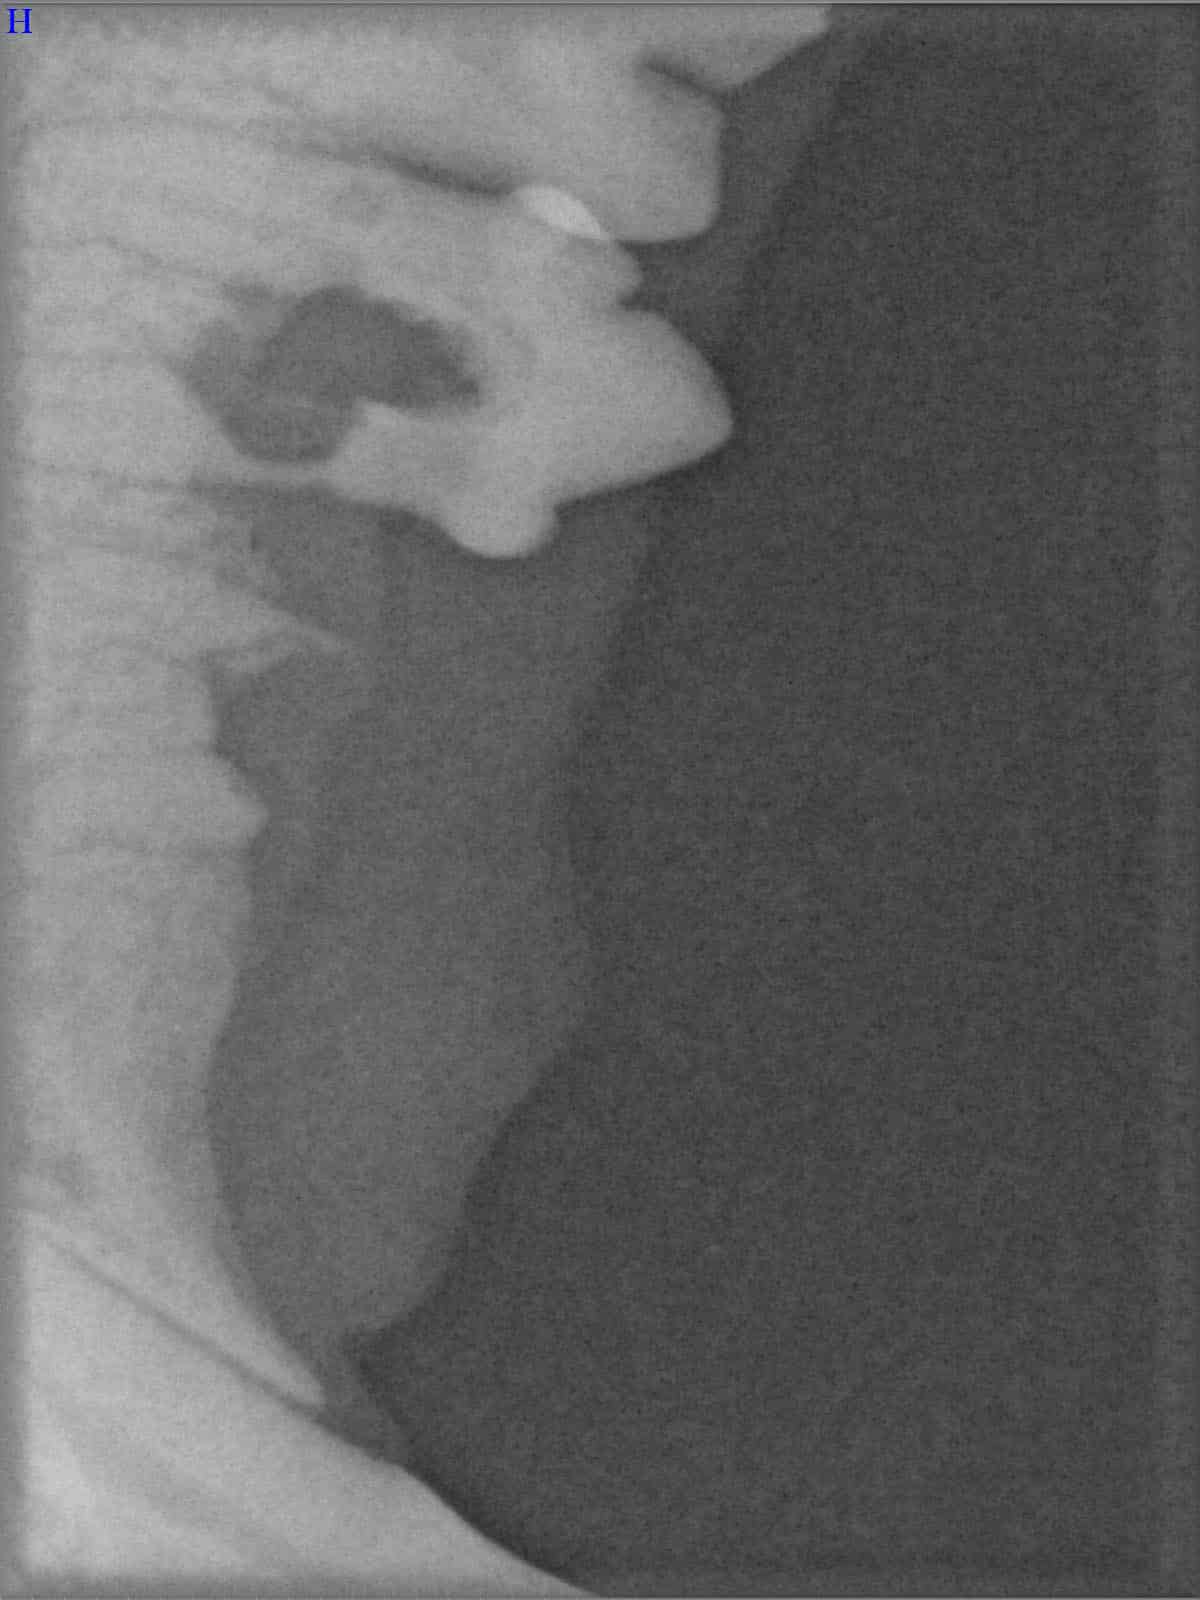

Röntgenbilder

(Fraktur + Wurzelentzündung durch Zahnstein)